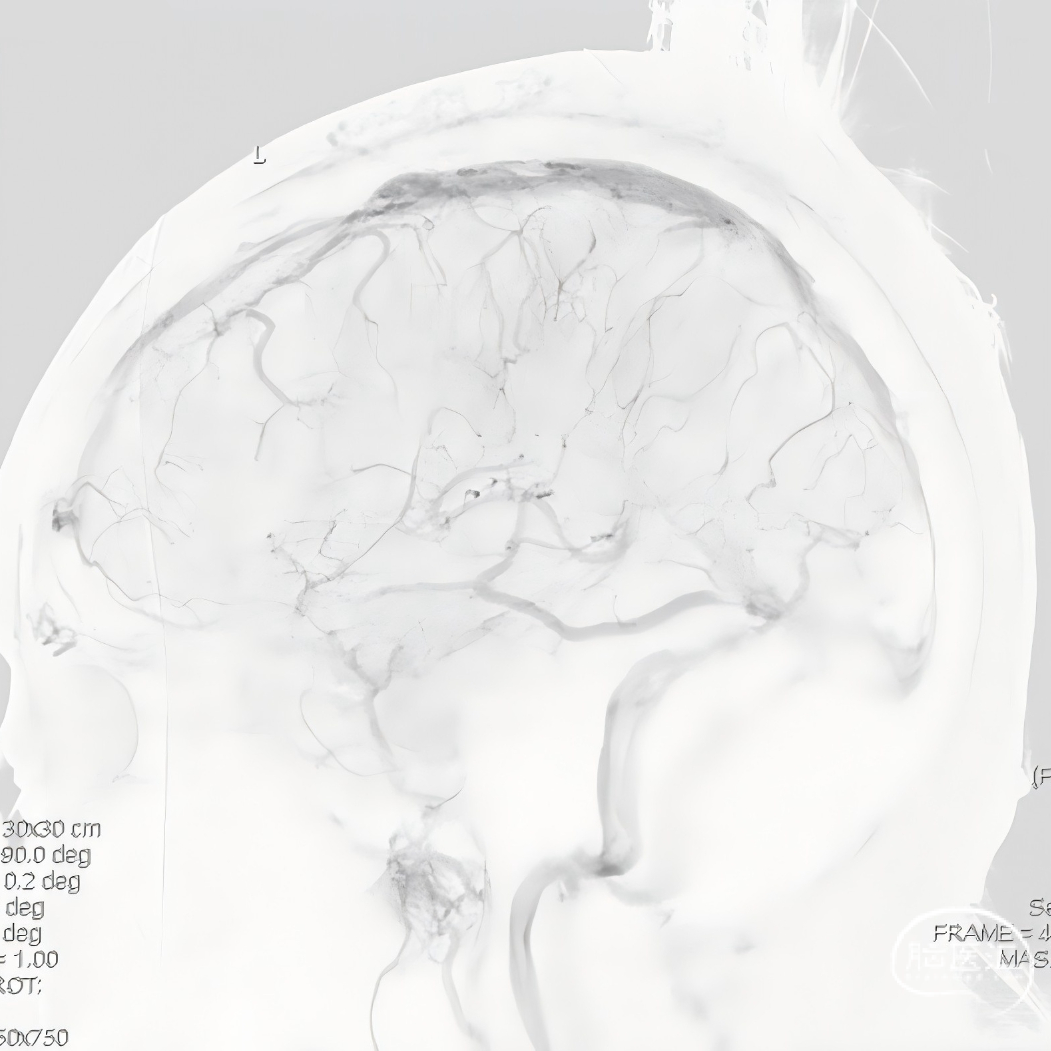

术前CTV:左侧颈内静脉、乙状窦、横窦闭塞,血栓形成。

术前高分辨核磁+黑血技术提示为急性期血栓。

术前MRV提示血栓负荷不断增加。

术前复查MRV提示血栓累及范围继续扩大。